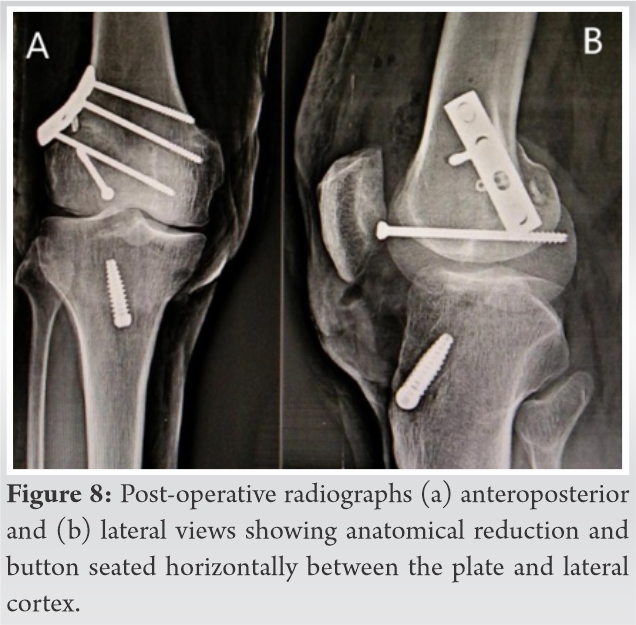

Two months after the surgery, the patient met with a road traffic accident and fell from a moving motorcycle with twisting injury to the same knee. The patient presented to us 7 days later with severe pain, even on slight movement, moderate effusion in the right knee with an inability to bear weight. Lachman and varus and values stress test were positive. An anteroposterior radiograph revealed a double joint line sign of lateral femoral condyle with the button sunk inside the lateral femoral cortex. Oblique radiograph confirmed a fracture passing through the femur tunnel with the button inside the fracture (Fig. 2). MRI showed a spiral displaced fracture of the lateral femoral condyle (Fig. 3), intact but lax graft fibers, and a button artifact inside the fracture line with intact medial collateral ligament and lateral collateral ligament (Fig. 4).